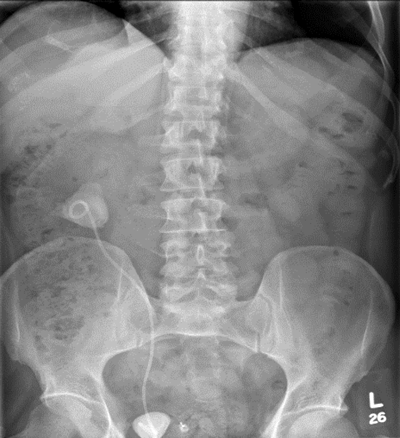

Figure 4.

A percutaneous puncture removed the stent, the radiological nephrostomy tube was removed and a 16F urethral catheter was inserted as a permanent nephrostomy in a patient who was now dialysis dependent (Figure 4). The patient bled post-procedure requiring embolisation (Figure 5).